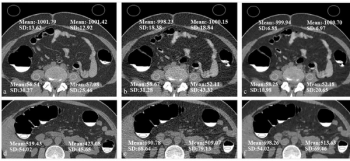

Emerging research suggests that a computed tomography (CT)-based radiomics model can predict FOXM1 expression and is independently prognostic for clear cell renal cell carcinoma.